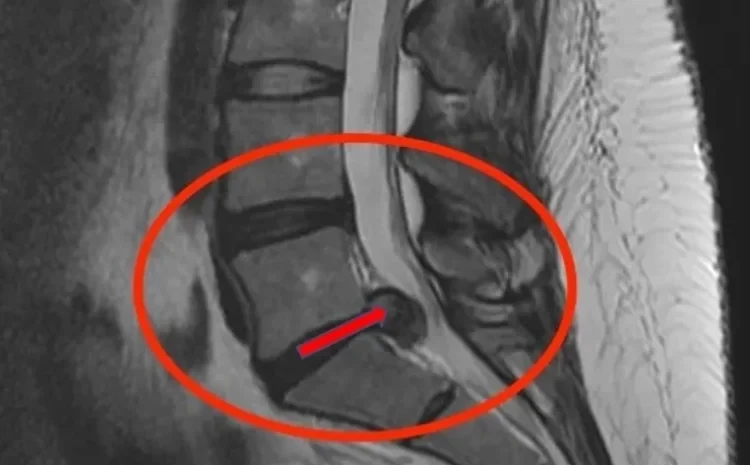

Possui hérnia de disco Lombar (L4/ L5/S1) ou Cervical. Nervo ciático inflamado

O tratamento se baseia em um diagnóstico mecânico para identificar a direção do movimento que centraliza a dor e alivia a pressão sobre o nervo. Utilizamos técnicas manuais especializadas (Terapia Mecânica – MDT) e exercícios específicos para reposicionar o disco intervertebral e promover a cicatrização natural da lesão. Este método é reconhecido internacionalmente e recomendado por especialistas em coluna em todo o mundo.